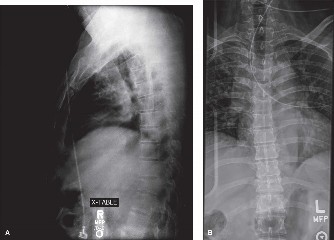

Pre-Operative Planning, Templating, and Patient Positioning

When surgical intervention becomes unavoidable, meticulous pre-operative planning is the cornerstone of a successful outcome. Advanced imaging is non-negotiable. An MRI with and without gadolinium contrast is the gold standard for defining the extent of the epidural abscess, the degree of neural compression, and the involvement of adjacent paraspinal musculature (e.g., psoas abscess). T1-weighted images typically show hypointense signals in the infected marrow, while T2-weighted and STIR sequences reveal hyperintense fluid and edema in the disc space and vertebral bodies. Gadolinium enhancement highlights the vascularized inflammatory phlegmon and the capsule of any abscesses.

In addition to MRI, a fine-cut computed tomography (CT) scan is essential for evaluating bony destruction. CT allows the surgeon to assess bone stock for pedicle screw purchase and to template the size of the interbody cages required for anterior column reconstruction. Upright standing radiographs (if the patient can tolerate them) or full-length supine films are necessary to evaluate global spinal alignment and regional kyphosis.

To contextualize the decision-making algorithm, consider the classic presentation of a middle-aged patient with multiple medical comorbidities. A paradigmatic case involves a 48-year-old obese female (Body Mass Index of 43) with poorly controlled diabetes mellitus who presents with severe, unrelenting low back pain, fevers, and chills. Advanced imaging, specifically magnetic resonance imaging (MRI), typically demonstrates discitis involving the L4–5 disc space with adjacent osteomyelitis of the L4 and L5 vertebral bodies. Crucially, in many early or medically responsive cases, there is an absence of epidural abscess formation, and standing radiographs reveal relatively normal sagittal and coronal alignment. When such a patient is neurologically intact—lacking saddle anesthesia, bowel/bladder incontinence, or upper motor neuron signs—the immediate clinical imperative shifts from urgent surgical decompression to aggressive pathogen identification and targeted antimicrobial therapy.